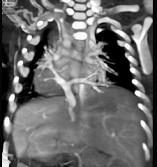

问题 女性,21岁,活动后呼吸困难,时常发生上呼吸道感染,CT扫描如图所示,请选择正确的选项 ( )

选项 A、该病人肺静脉异位引流入下腔静脉 B、该病人为心下型肺静脉异位引流 C、肺静脉异位引流根据引流肺静脉支数的不同可分为部分性及完全性 D、根据引流部位不同分为心上型、心脏型、心下型 E、考虑为肺静脉异位引流

答案 ABCDE